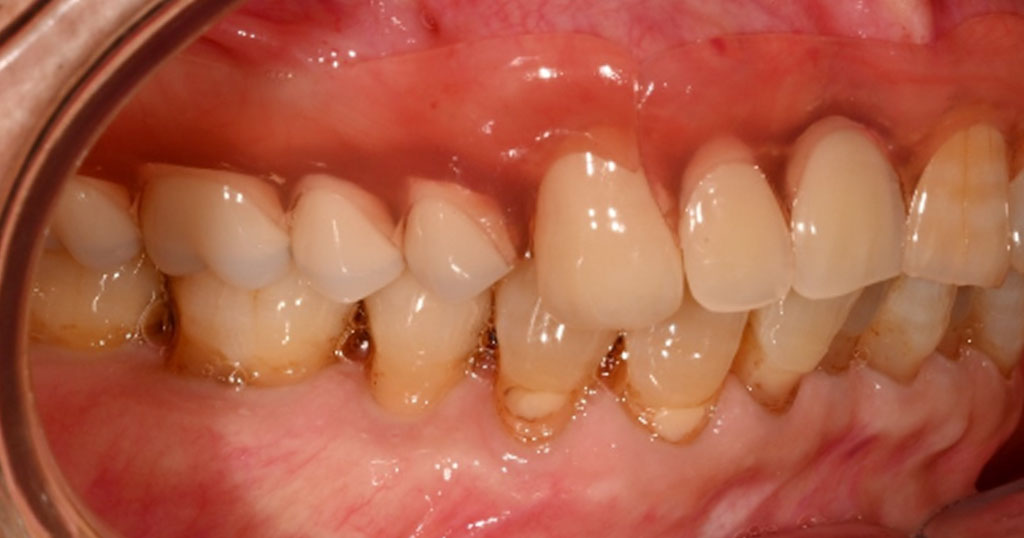

Before2

80代男性。上顎右124567番が欠損した状態で来院。今まで使用していた保険の入れ歯を使用しているが不満で、インプラント手術も怖いということで自費の入れ歯をご希望とのこと。

金属部分がない、フィット感がある、入れ歯を支える歯への負担を軽減させるため、上顎右124567番の欠損を補う着脱が簡単なコンティースを作成